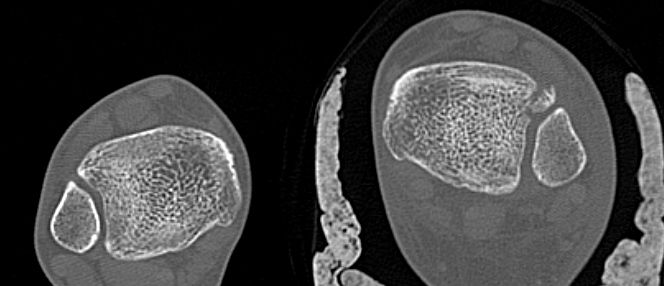

CT

Normal bilateral axial CT

Bilateral axial CT

- compare to other side

- widening

- malrotation

- posterior malleolar fracture / Volkmann tubercle

- anterior tubercle / Tillaux-Chaput tubercle

Gifford's tibiofibular line (TFL)

- anterolateral fibula

- should be < 2 mm from tibia

< 4 mm Tibio-fibular gap

Normal Gifford's line and tibiofibular gap

Abormal Gifford's line and increased tibiofibular gap with posterior malleolar fracture

Tillaux-Chaput fracture on right with mild increased widening